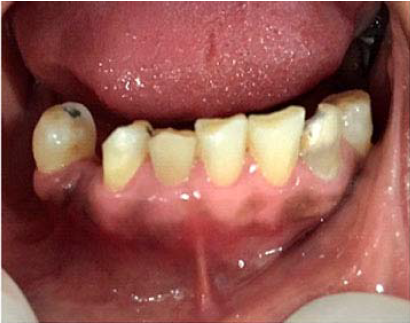

Se realizó instrumentación del sistema de conductos hasta longitud de trabajo y se colocó hidróxido de calcio como medicación intracanal, se programa una próxima cita a los 7 días después, no obstante la paciente acude 48 horas después refiriendo dolor severo alrededor de 24 horas posteriores a la intervención, al examen clínico se aprecia inflamación y perdida de contorno gingival a nivel dientes anteroinferiores derechos (Figura 1).

Por tal motivo se retoma el tratamiento previa anestesia e irrigación con hipoclorito de sodio y se formula a la paciente analgésicos y antibióticos, así como una inyección intramuscular de 4mg de dexametasona, una vez controlado el dolor se programa nueva cita en 5 días; en esta se anestesia nuevamente, se realiza aislamiento absoluto, no se aprecia contenido purulento dentro del conducto por lo cual se procede a instrumentar hasta longitud de trabajo, al no encontrarse tope apical, se decide colocar Mineral Trióxido Agregado (MTA) para crear tapón apical en los últimos 4mm de la raíz y posteriormente se obtura el resto del conducto con gutapercha en otra cita y el diente es restaurado (Figura 2).

Se realiza un control clínico y radiográfico a los 15 días y se observa disminución de la lesión, además la paciente se encuentra asintomática (Figura 3).